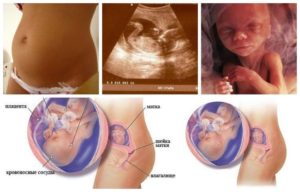

Копчико-теменной размер плода на 17 неделе беременности достигает в среднем 13 см, а вес может доходить до 140 г. Кроха уже такой большой, как раскрытая ладонь взрослого человека. Он очень быстро растет и развивается и на 17 неделе беременности уже слышит доносящиеся извне звуки, узнает голоса, ощущает ваши эмоции и настроение.

Наступает время спокойного и радостного ожидания, когда носить малыша ещё не тяжело, но уже очевидно, что он есть и проявляет собственную, независимую от мамы активность. Длина малыша – около 12 см, однако он выглядит практически также, как будет выглядеть при рождении.

Размер плода или его рост – 12-20 см в длину, вес – 100-150 грамм. Это вес и размер средней груши. Однако, живот становится заметен. Плацента значительно утолщается, вес её теперь около 500 граммов. Толще плацента – больше кровеносных сосудов, питающих плод. Он активно потребляет нужные вещества и активно растёт.

Размер плода на 17 неделе беременности составляет около 11-14 см в длину, а его вес – чуть более 100 граммов. Таким образом, на 17 неделе беременности размер плода можно сравнить с крупной грушей.

Плацента представляет собой толстый и плотный слой ткани, который через пуповину связан с плодом. Толщина плаценты в среднем составляет 17 мм. Плацента пронизана разветвленной сетью сосудов, благодаря чему снабжает малыша кислородом и другими необходимыми питательными веществами.